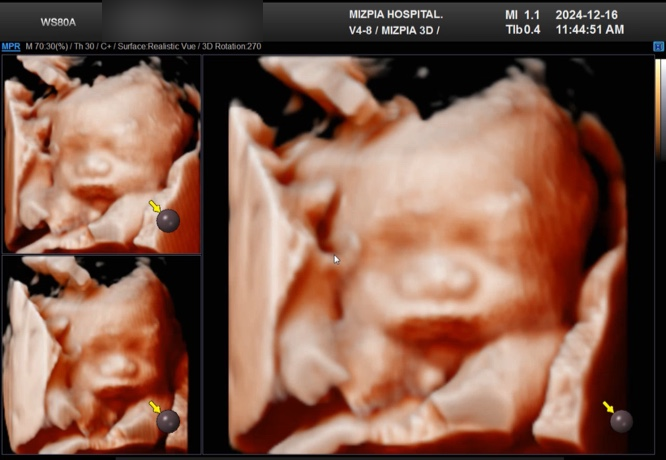

[임신일기] 자주 방문하는 듯한 정기검진(27주6일)

임신 초기엔 4주 텀이라 한방이가 잘 있는지 궁금했는데, 요즘 이벤트들이 있어서 그런지 1~ 2주 이렇게 방...